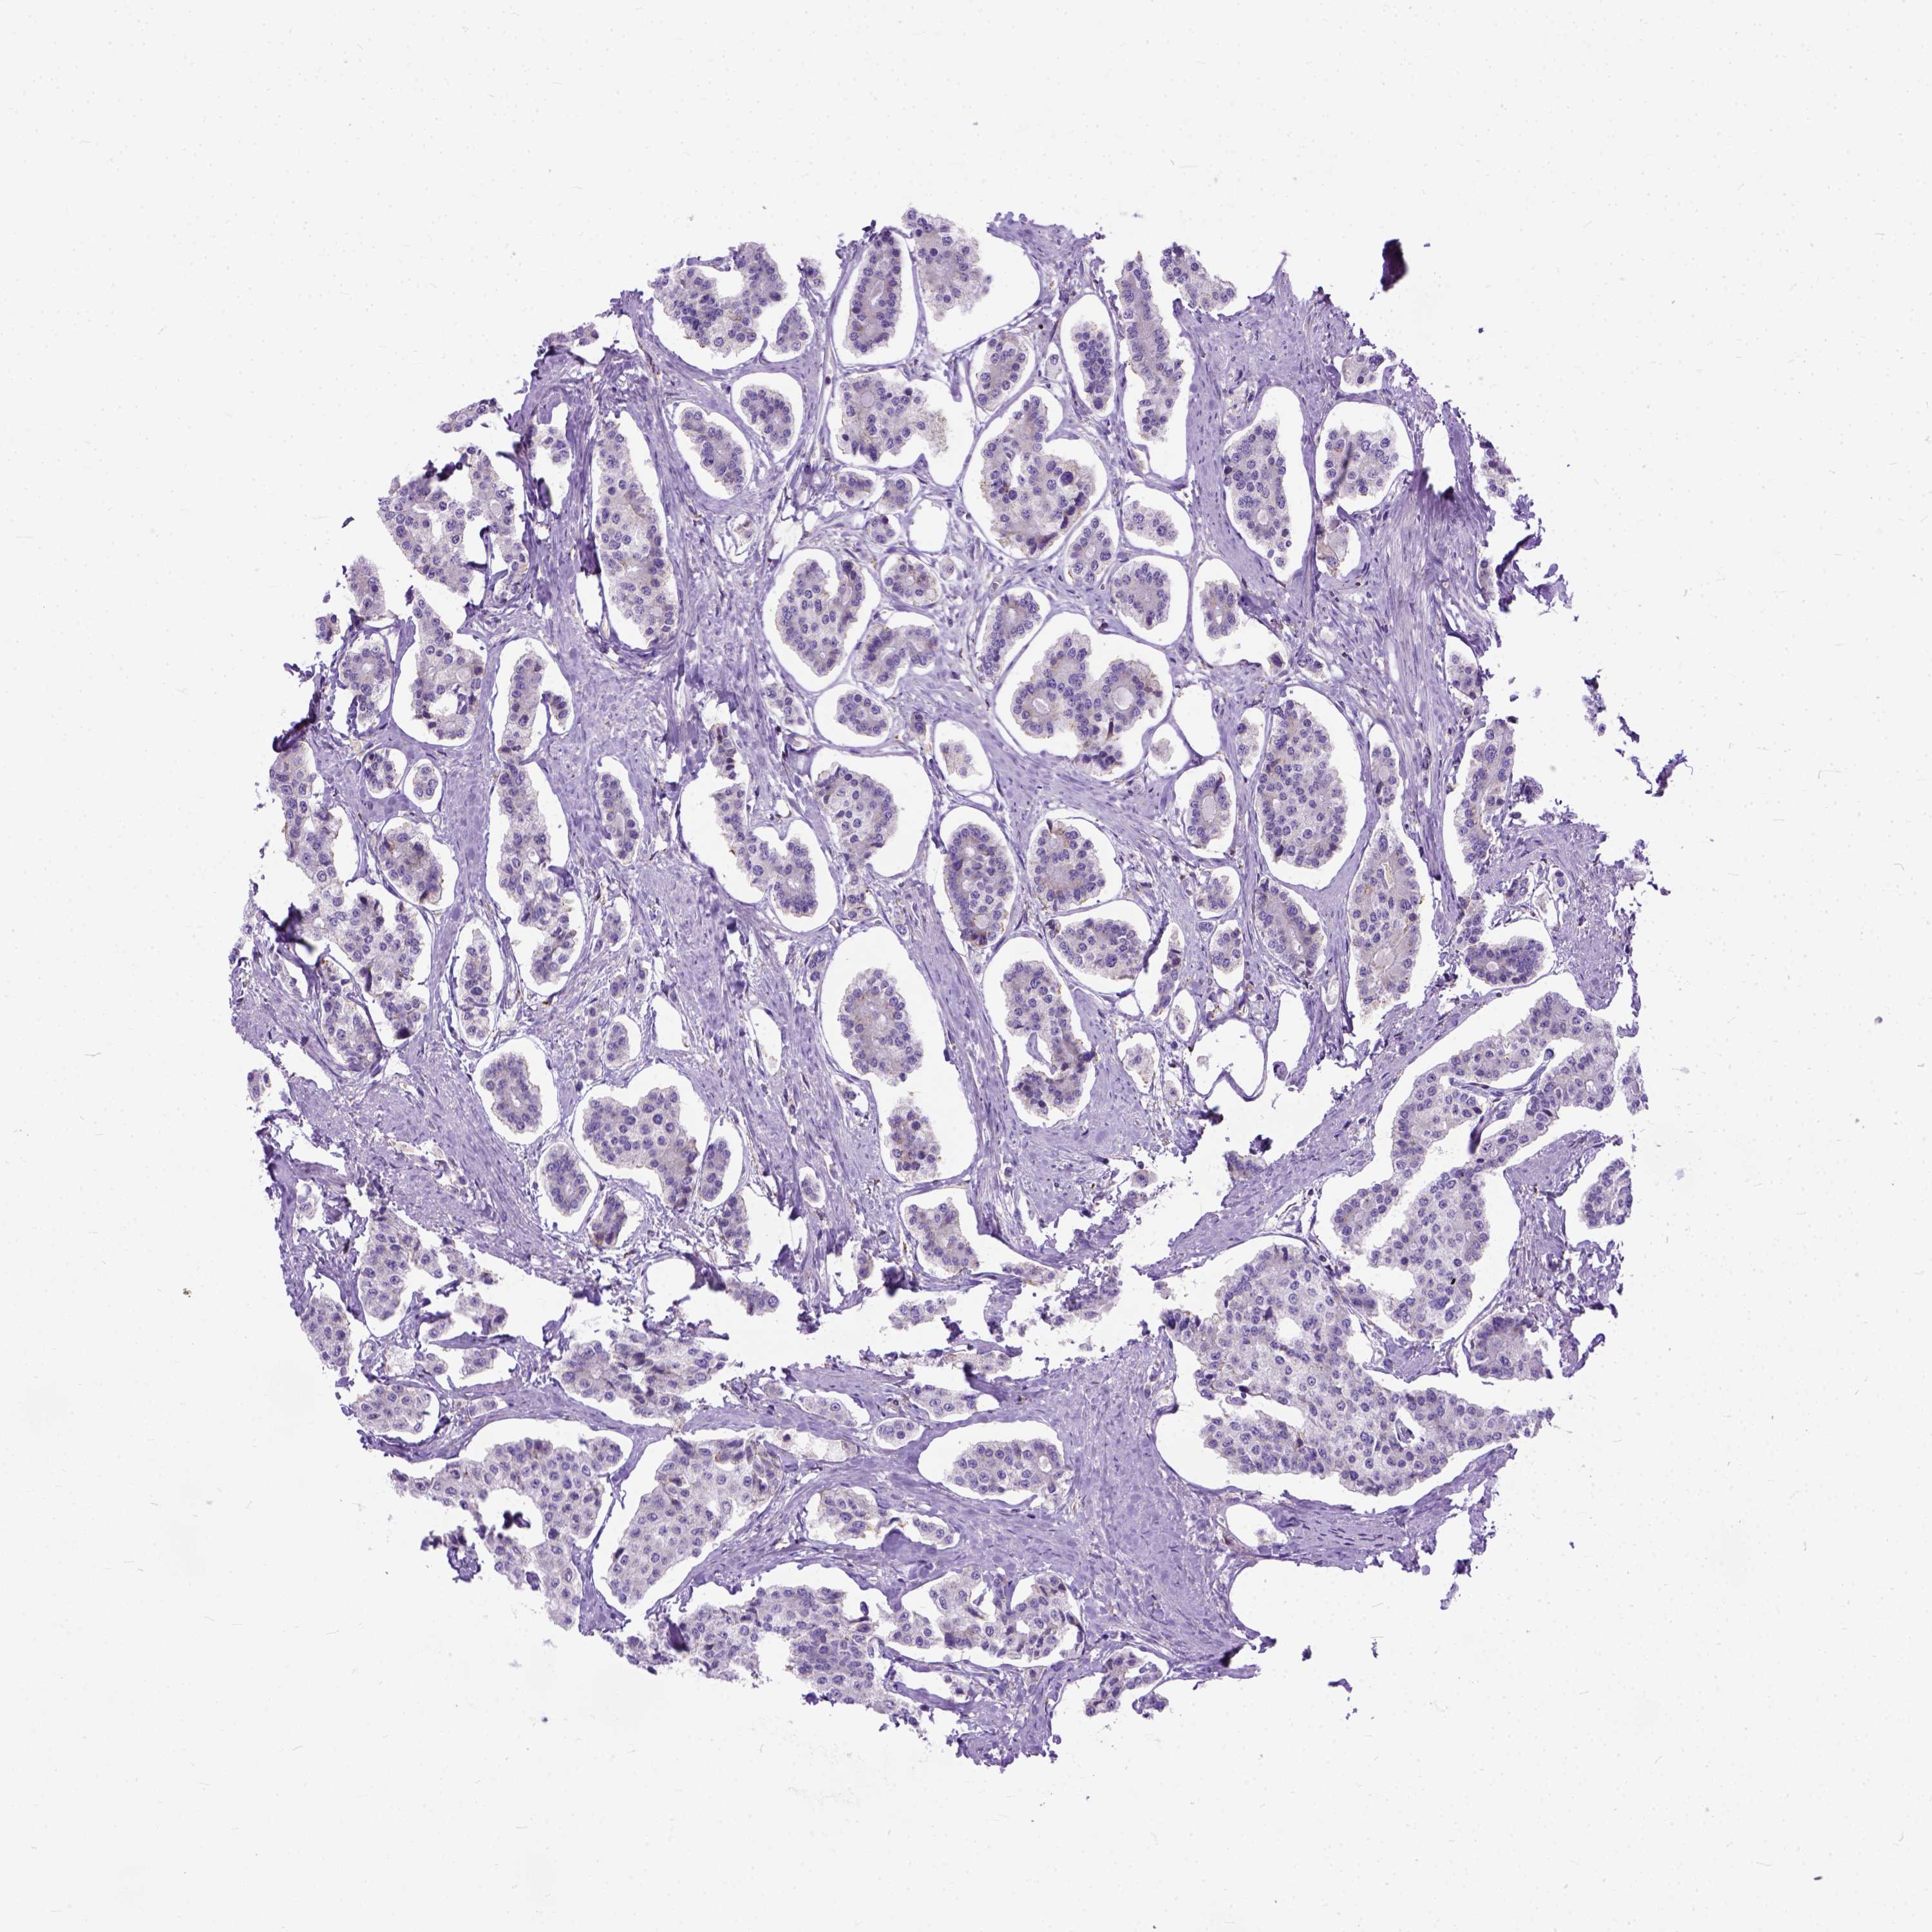

CARCINOID - Protein expressioni

A mouse-over function shows sample information and annotation data. Click on an image to view it in a full screen mode. Samples can be filtered based on level of antibody staining by selecting one or several of the following categories: high, medium, low and not detected. The assay and annotation is described here.

Antibody stainingi

Antibody staining in the annotated cell types in the current human tissue is reported as not detected, low, medium, or high, based on conventional immunohistochemistry profiling in selected tissues. This score is based on the combination of the staining intensity and fraction of stained cells.

Each image is clickable and will lead to virtual microscopy that enables deeper exploration of all samples and also displays staining intensity scores, fraction scores and subcellular localization as well as patient and tissue information for each sample.

Antibody HPA035026

Antibody HPA043198

Staining

High

Medium

Low

Not detected

Intensity

Strong

Moderate

Weak

Negative

Quantity

>75%

75%-25%

<25%

None

Location

Nuclear

Cytoplasmic/membranous

Cytoplasmic/membranous,nuclear

Carcinoid, malignant, NOS

Carcinoma, NOS